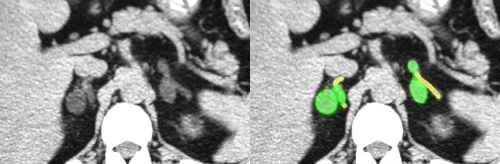

![]() In this instance the adrenal size is clearly abnormal. The abnormal areas of metastatic disease are overlayed in green. The thickening of the medial limb of the right and the mass on the left result in an increased size of the each of adrenal glands. Courtesy of: Ashley Davidoff, M.D. |

![]() This case shows bilateral nodularity caused by bilateral adrenal adenomas. The abnormal areas are overlayed in green and the normal adrenal outlined in yellow. Images courtesy of: Ashley Davidoff, M.D. adrenals-00031 |

The tiny subcentimeter green nodule at the apex of the left adrenal is a surgically proven aldosteronoma, which is a benign tumor that produces excessive aldosterone and causes hypertension. If left untreated, devastating effects of hypertension result. Courtesy of: Ashley Davidoff, M.D. |

This case shows bilateral nodularity caused by bilateral adrenal adenomas. The abnormal areas are overlayed in green and the normal adrenal outlined in yellow. Courtesy of: Ashley Davidoff, M.D. |

In this CT scan, the green overlay is a soft tissue nodule that was found incidentally. Courtesy of: Ashley Davidoff, M.D. |

The nodule is oval, with smooth borders, measures less than 3cm., (left image) and has a density of 2.6 HU. (right image) It is a classical “incidentaloma” or benign adenoma. No further workup is needed. Courtesy of: Ashley Davidoff, M.D. |

The finding of bilateral masses (green overlay), in a patient with a known malignancy most likely represents metastatic disease. This patient has known lung carcinoma and bilateral masses with peripheral enhancement, which almost certainly represents metastatic disease. Courtesy of: Ashley Davidoff, M.D. |